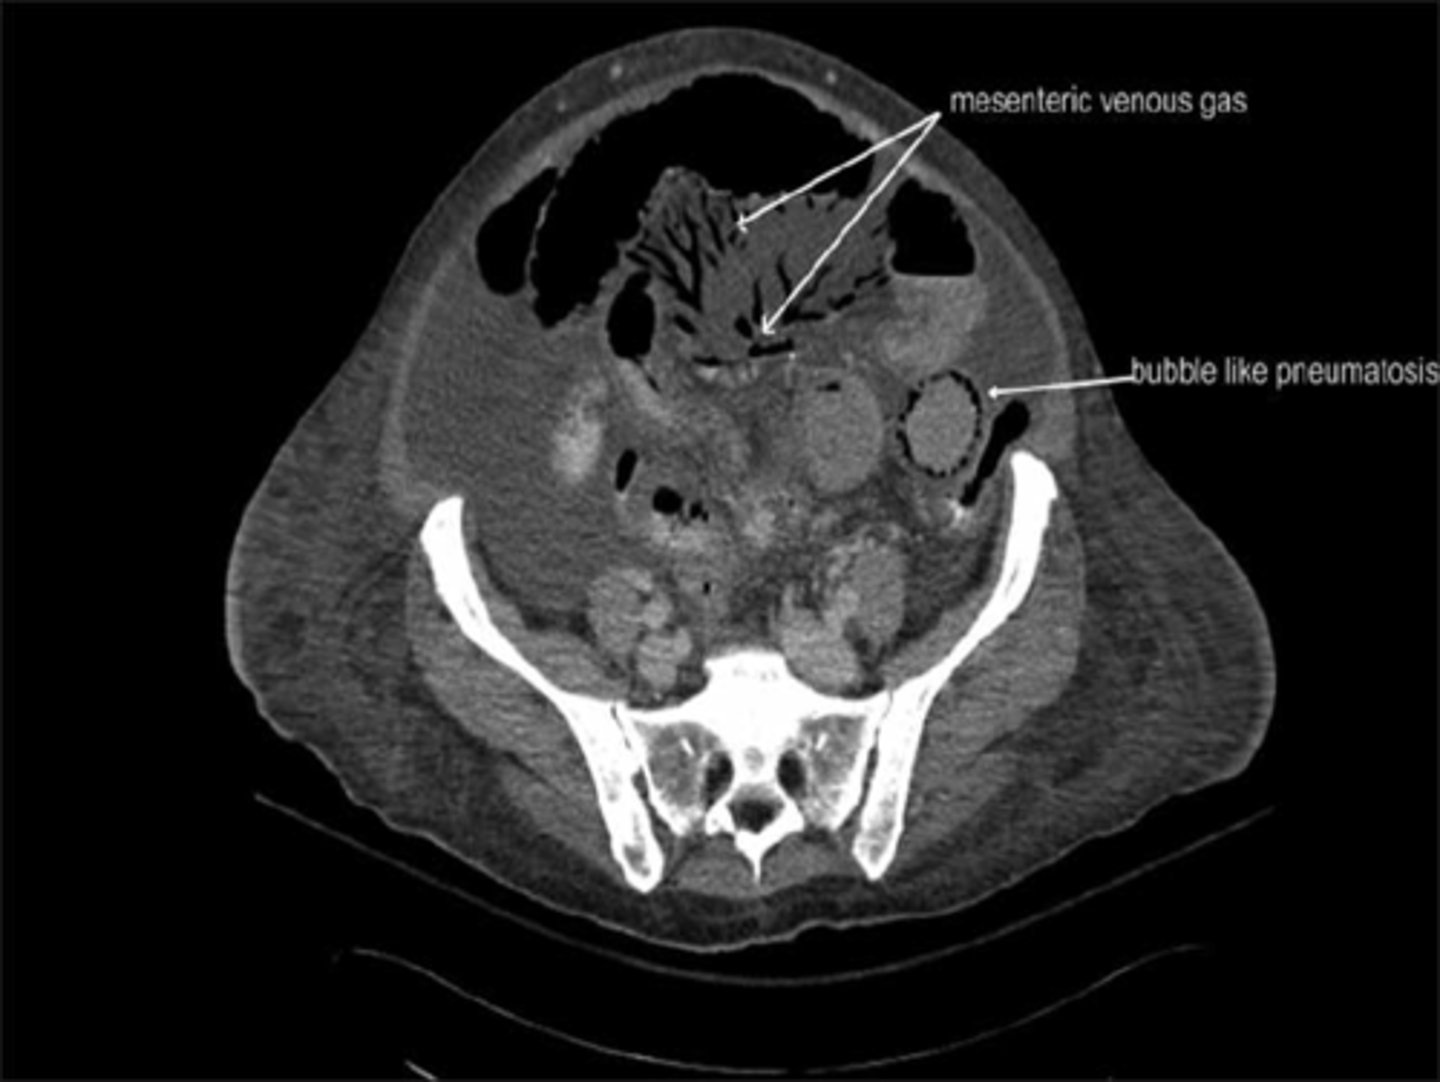

Pneumatosis cystoides intestinalis.

SOLID WHITE ARROWS:

Clusters of air-containing CYSTs associated with the left colon.

Portal air in liver secondary to pneumatosis